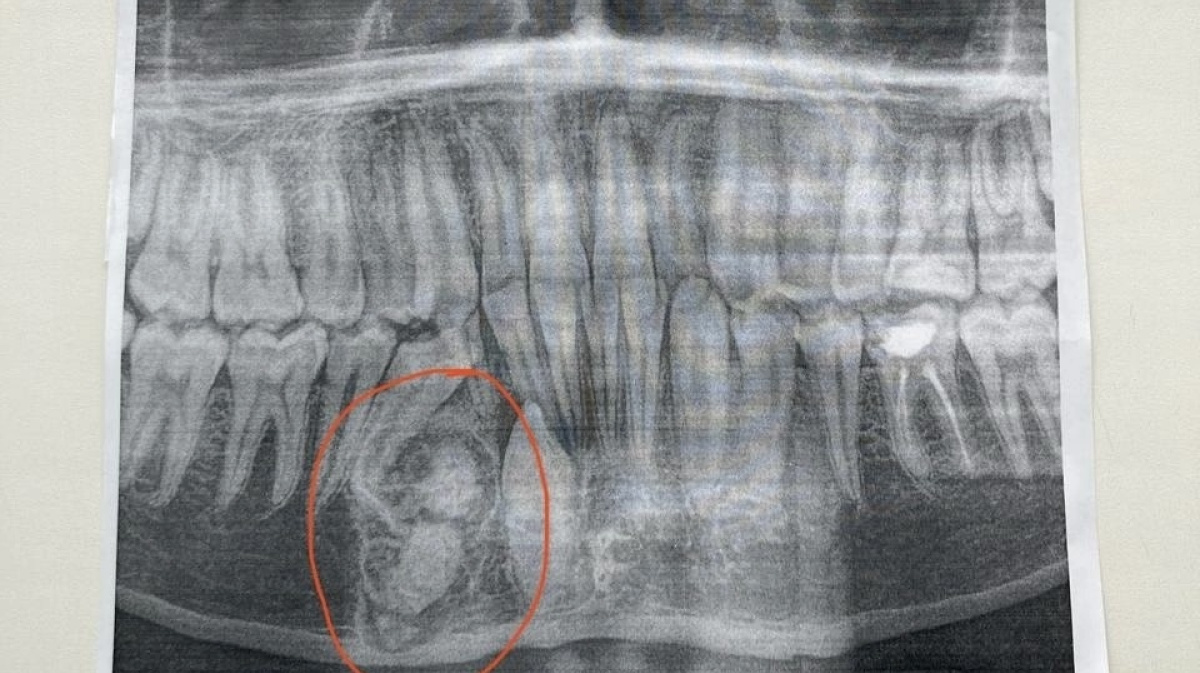

Рак Зуба Фото

Рак Зуба Фото 116 фото